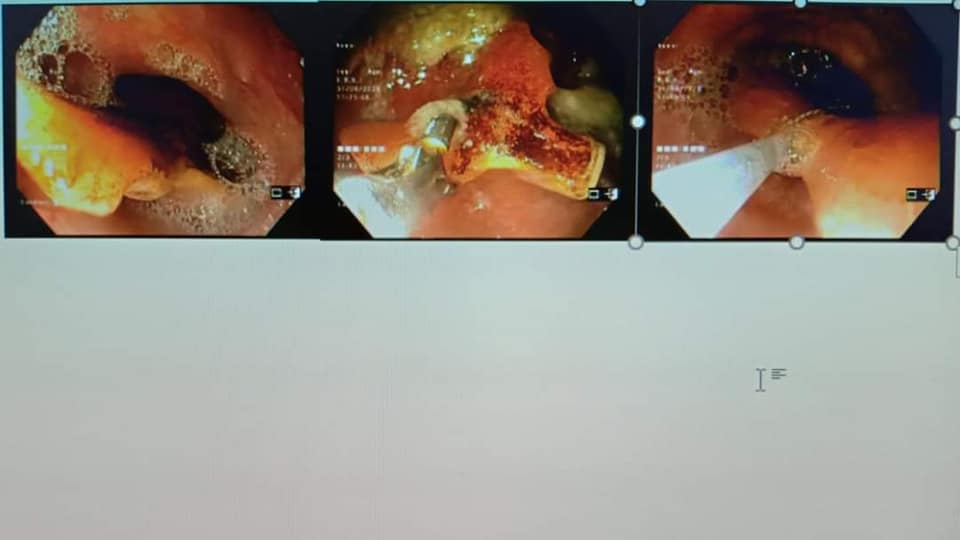

Ngày 31/8/2020 Bệnh viện đa khoa Sơn Tây đã làm thủ thuật lấy dị vật Răng giả rơi mắc ở thực quản thành công tại khoa Nội soi tiêu hóa- Bệnh viện đa khoa Sơn Tây thực hiện. Bệnh nhân Nguyễn Duy H 62 tuổi Trung Hưng- Sơn Tây đến bệnh viên ĐK Sơn Tây khám trong tình trạng mắc vướng khó chịu ở họng kèm ho kéo dài và điều trị không khỏi. Qua khám khai thác bệnh nhân cho biết sáng nay 31/8/2020 ăn cơm, uống thuốc thì bị rơi răng giả cảm giác nghẹn ở cổ khó chịu tím tái. Ngay sau đó bệnh nhân đến khám BV Sơn Tây nghi có dị vật đường tiêu hóa được các bác sỹ cho đi làm Nội soi Thực quản dạ dày… Kết quả Nội soi phát hiện có dị vật nằm ngang ở 1/2 Thực quản (dị vật có 3 cạnh) mắc vào thành TQ , thực quản sưng nề đỏ có điểm trợt loét do tình trạng viêm quá nghiêm trọng . Trước tình hình đó các Bác sỹ khoa Nội soi đã hội chẩn lãnh đạo bệnh viện & giải thích cho người nhà bệnh nhân là có dị vật mắc ở trong TQ cần lấy ra. Dưới sự chỉ đạo của đồng chí Giám đốc Ts Đặng Đức Hoàn các bác sĩ xác định đây không là 1 dị vật không đơn thuần (vì dị vật to có 3 cạnh), rất nguy hiểm và đòi hỏi phải được xử lý ngay nếu không sẽ để lại một số biến chứng nặng nề như chảy máu, tạo ổ áp xe, thủng trung thất hoặc đâm vào và làm tổn thương những động mạch có kích thước lớn xung quanh thực quản. Vậy cần phải gây mê cho bệnh nhân để đưa dụng cụ vào tiếp xúc dị vật đẩy xuôi xuống rồi dùng giỏ gắp ra. Sau khi tiến hành xong thủ thuật gắp ra là 1 răng giả có kt (2,5 x 2,5×1,5) cm bệnh nhân ổn đinh, vào viện điều trị bảo tồn vết thương sây sát họng- thực quản. Qua đây cho thấy mắc dị vật đường tiêu hóa như hóc xương, răng giả… hoặc hóc đồ ăn là tình trạng cấp cứu đường tiêu hóa nguy hiểm, có khả năng dẫn đến những biến chứng gây nguy hiểm cho tính mạng người bệnh. Vì vậy, để tránh dị vật đường tiêu hóa thì bệnh nhân cần có thói quen ăn uống khoa học, tránh để dị vật có cơ hội đi vào đường tiêu hóa và ngay khi có những triệu chứng nghi ngờ thì cần đến ngay cơ sở y tế để được phát hiện và có biện pháp điều trị nhanh nhất trước khi bệnh diễn biến nặng nề hơn. Nhưng đến với Bệnh viện ĐK Sơn Tây với đội ngũ bác sỹ điều dưỡng… vững về Y thuật, Tâm sáng trong & tập thể đoàn kết đồng lòng cùng chí hướng thì chắc chắn người dân trong khu vực sẽ được hưởng các dịch vụ kỹ thuật mới tiến bộ ngay tại bệnh viện Sơn Tây này mà không cần phải về bệnh viện trung ương.